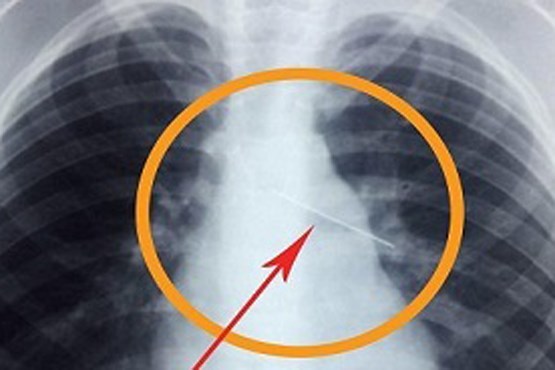

خارج کردن سوزن ۴ سانتی از کبد نوزاد ۱۱ ماهه

به گزارش میزان، تیم پزشکی بیمارستان پیامبر اعظم (ص) شهر قشم، سوزن 4 سانتی را از کبد و شکم کودکی 11 ماهه خارج کردند.

بعد از معاینههای پزشکی و آزمایشات مختلف، سوزن از بدن این نوزاد خارج شد.